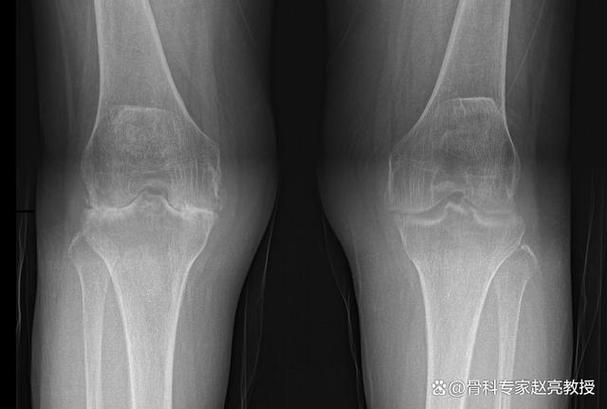

- 膝关节:承受着身体的重量,是RA最常累及的大关节之一,严重的膝关节破坏会导致患者无法站立和行走。

遵医嘱定期回医院复查,通过X光片等检查评估假体的位置、磨损情况以及有无松动迹象。